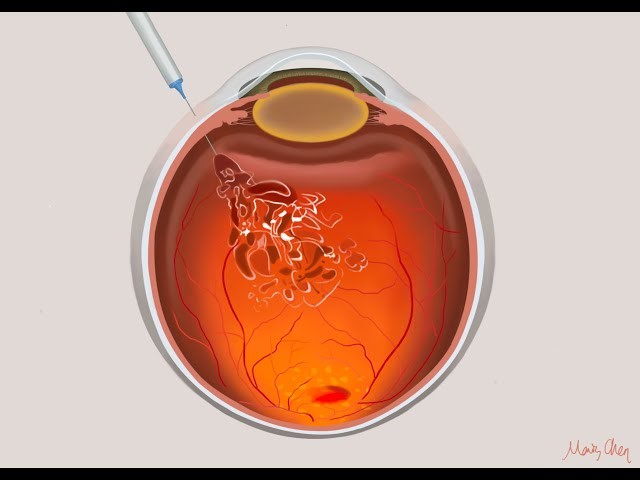

Ενδουαλοειδικές εγχύσεις (ενέσεις)

Αποτελούν μικροεπέμβαση κατά την οποία εγχύεται στο πίσω μέρος του ματιού (υαλοειδές σώμα) κατάλληλο φάρμακο, ανάλογα με την πάθηση του ασθενούς και με την βοήθεια κατάλληλης μικροβελόνας. Οι εγχύσεις πραγματοποιούνται σε προσαρμοσμένο χώρο, συνήθως χώρο χειρουργείων, ώστε να επιτευχθούν οι απαραίτητες συνθήκες ασηψίας για τον ασθενή. Είναι πράξη που περιλαμβάνει την χορήγηση τοπικού αναισθητικού για να ελαχιστοποιηθεί ο πόνος, ενδελεχή καθαρισμό της περιοχής των βλεφάρων και εν συνεχεία την έγχυση του φαρμάκου. Η διαδικασία δεν απαιτεί πολύ χρόνο, αλλά καλή συνεργασία για να αποφευχθούν επιπλοκές.

Τι περιλαμβάνουν οι ενδοϋαλοεδικές εγχύσεις;

Συνηθέστερες αιτίες που απαιτούν αυτού του είδους θεραπεία είναι η ηλικιακή εκφύλιση της ωχράς κηλίδας, το διαβητικό οίδημα της ωχράς κηλίδας και η αγγειακές αποφράξεις. Τα φάρμακα που χρησιμοποιούνται είναι αντιαγγειογενετικοί παράγοντες (anti-VEGF), όπως το aflibercept, το ranibizumab και το bevacizumab ή νεότερα, όπως το faricimab. Η δράση τους έγκειται στην αναστολή της δημιουργίας εύπλαστων παθολογικών αιμοφόρων αγγείων (νεοαγγείων) και στη μείωση του  ενδοαμφιβληστροειδικού ή υπαμφιβληστροειδικού υγρού, που τα νεοαγγεία δημιουργούν καθώς διαρρέουν, κυρίως στην περιοχή της ωχράς κηλίδας.  Οι εγχύσεις μπορεί επίσης να περιλαμβάνουν κορτιζόνη (κυρίως για ανθεκτικές περιπτώσεις ή όταν οι αντιαγγειογενετικοί παράγοντας αντενδείκνυνται) και τα αντιβιοτικά (π.χ. για ενδοφθαλμίτιδα).

Έγχυση φαρμάκου anti-VEGF ενδοϋαλοειδικά